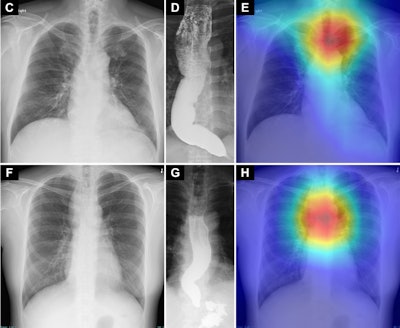

Saliency maps using Grad-CAM++ (E and H) show the model’s point of interest in chest radiographs (C and F) of patients with achalasia. The model’s point of interest is highlighted with red, yellow, and green. In both the upper and lower panels (E and H), the point of interest is located in a region around the upper esophagus that corresponds to an air esophagogram and/or air-fluid level in the esophagus in the barium esophagogram (D and G). Osaka Metropolitan University. Image available for republishing under Creative Commons license (CC BY-NC-ND 4.0)